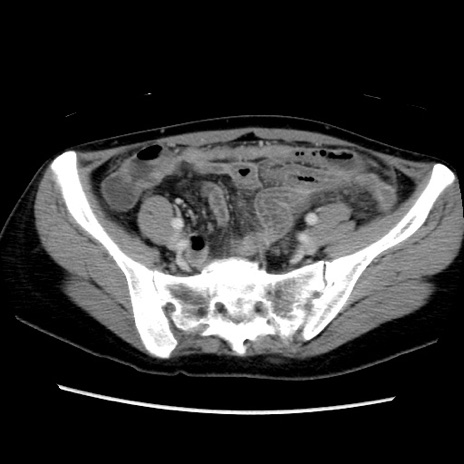

症例39(横断像)

【症例】40歳代女性

【主訴】上下腹部痛

【現病歴】2日目から下腹部痛あり。夜間は痛みで眠れなかった。昨日より上腹部痛と下痢が出現。臥位で痛みは軽快したため、休んでいた。本日になって臥位でも立位でも痛みが強くなってきたため救急要請。

【既往歴】子宮内膜症

【身体所見】部:平坦・軟、左上下腹部に圧痛あり、反跳痛あり。

【データ】WBC 21800、CRP 26.78